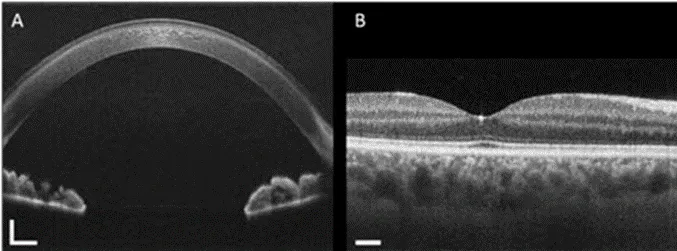

健康人眼的角膜和虹膜(A)以及视网膜组织(B)的横截面如下图所示。颜色深度的改变意味着反射光的强度改变,说明内部材料发生变化。